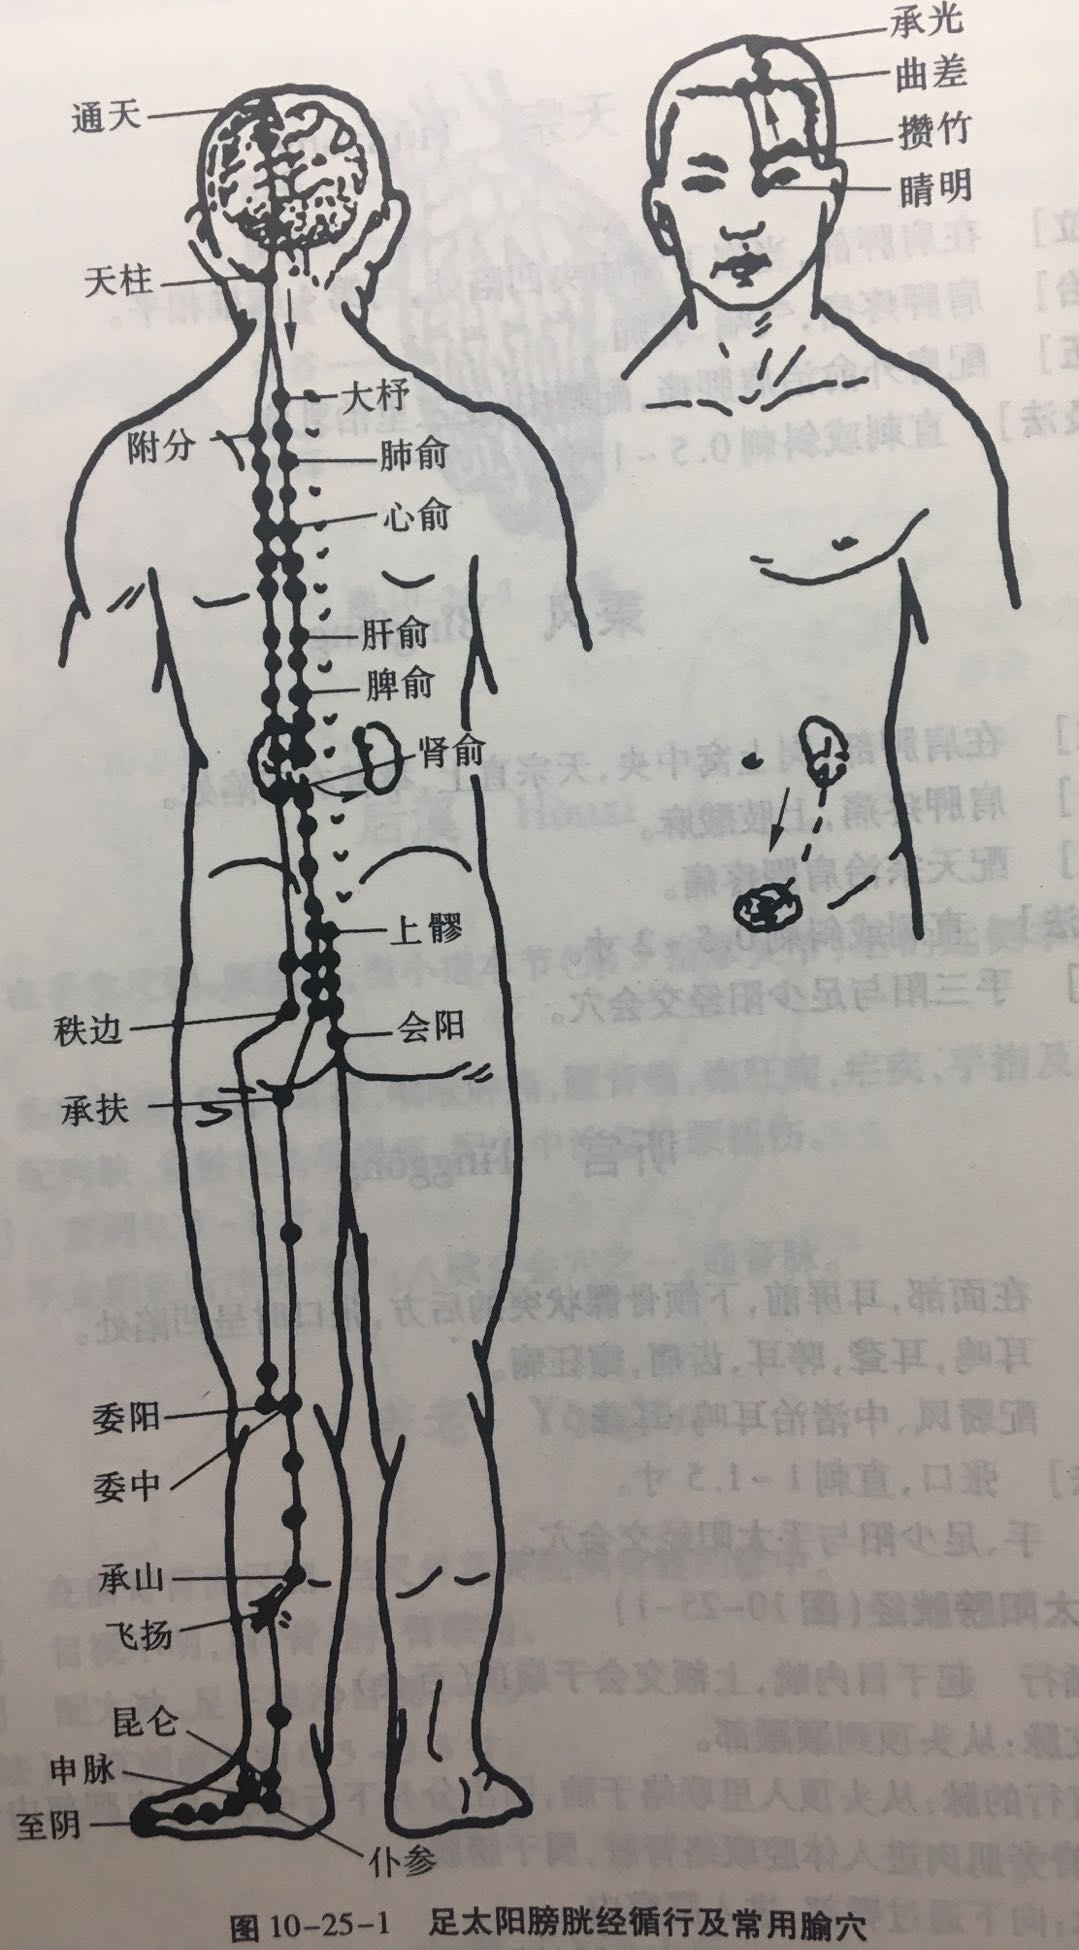

【(七)足太阳膀胱经(图 10-25-1)】

2、歌诀 足太阳经六十七,精明目内红肉藏,攒竹眉冲与曲差,五处上寸半承光,通天络却玉枕昂,天柱后际大筋外,大杼(zhù)背部第二行,风门肺俞厥阴四,心俞督俞膈俞强,肝胆脾胃俱挨次。三焦肾气海大肠,关元小肠到膀胱,中膂(lǚ)白环仔细量,自从大杼至白环,各各节外寸半长,上髎次髎中复下,一空二空腰髁当,会阳阴尾骨外取,附分侠脊第三行,魄户膏肓与神堂。噫嘻膈关魂门九,阳纲意舍仍胃仓。肓门志室胞肓续,二十椎下秩边场,承扶臀横纹中央,殷门浮郗到委阳,委中合阳承筋是,承山飞扬踝附阳。昆仑仆参连申脉,金门京骨束骨忙,通谷至阴小指旁。

3、经脉循行 起于目内眦,上额交会于于巅顶(百会)。

巅顶部支脉:从头顶到颞(niè)颥(rú)部。

巅顶部直行的脉:从头顶入里联络于脑,回出分开下行项后,沿肩胛部内侧,夹脊柱,到达腰部,从脊旁肌肉进入体腔联络肾脏,属于膀胱。

腰部支脉:向下通过臀部,进入腘(guó)窝内。

后项部支脉:通过肩胛骨内缘直下,经过臀部下行,沿大腿后外侧与腰部下来的支脉会和于腘窝中。从此向下,出于外踝后,第五趾骨粗隆,至小指外侧端(至阴),与足少阴经相接。

4、主要病候 小便不通,遗尿,癫狂,疟疾,目痛,见风流泪,鼻塞多涕,鼻衄,头痛,项、背、臀部及下肢循行部位痛麻等。

3、主治概要 主治头、项、目、背、腰、下肢部病证及神志病,背部第一侧线的背俞穴及第二侧线相平的腧穴,主治与其相关的脏腑病证和有关的组织器官病证。

晴明

【定位】 在面部,目内眦角稍内上方凹陷处(图 10-25-2)。

【主治】 目赤肿痛,流泪,视物不明,目眩,近视,夜盲,色盲。

【配伍】 配球后、光明治视物不明。

【刺灸法】 嘱患者闭目,医者左手轻推轻推眼球向外侧固定,右手缓慢进针,紧靠眶缘直刺 0.5 ~ 1 寸。不捻转,不提插(或之轻微地捻转和提插)。出针后按压针孔片刻,以防出血。本穴禁灸。

【附注】 手足太阳、足阳明、阴跷、阳跷五脉交会穴。

攒竹

【定位】 在面部,当眉头凹陷处,约在目内眦直上(图 10-25-2)。

【主治】 头痛 ,口眼歪斜,目视不明,流泪,目赤肿痛,眼睑瞤(rún)动,眉棱骨痛,眼睑下垂。

【配伍】 配阳白治口眼歪斜、眼睑下垂。

【刺灸法】 平刺 0.5 ~ 0.8 寸。禁灸。

天柱

【定位】 在项部大筋(斜方肌)外缘之后发际凹陷中,约当后发际正中旁开 1.3 寸。

【主治】 头痛,项强,鼻塞,癫狂痫,肩背病,热病。

【配伍】 配大椎治头痛项强。

【刺灸法】 直刺或斜刺 0.5 ~ 0.8 寸,不可向内上方深刺,以免伤及延髓。

风门

【定位】 在背部,当第 2 胸椎棘(jí)突下,旁开 1.5 寸。

【主治】 伤风,咳嗽,发热头痛,项强,胸背痛。

【配伍】 配肺俞、大椎治咳嗽、气喘,配合谷治伤风咳嗽。

【刺灸法】 斜刺 0.5 ~ 0.8 寸。

【附注】 足太阳经与督脉交会穴。

肺俞

【定位】 在背部,当第 3 胸椎棘突下,旁开 1.5 寸。

【主治】 咳嗽,气喘,吐血,骨蒸,潮热,盗汗,鼻塞。

【配伍】 配风门治咳嗽喘,配合谷、迎香治鼻疾。

【刺灸法】 斜刺 0.5 ~ 0.8 寸。

【附注】 肺的背俞穴。

肾俞

【定位】 在腰部,当第 2 腰椎棘突下,旁开 1.5 寸。

【主治】 遗尿,遗精,阳痿,月经不调,白带,水肿,耳鸣,耳聋,腰痛。

【配伍】 配太溪、三阴交治月经不调,配翳风,耳门治耳鸣、耳聋。

【刺灸法】 直刺 0.5 ~ 1 寸。

【附注】 (1)肾的背俞穴。(2)据实验观察:针刺对正常人水负荷后肾脏泌尿功能的影响,发现在大多数情况下,针刺肾俞或京门穴时可抑制肾脏的泌尿功能。